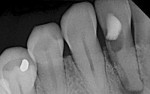

Organized roughened surfaces of specific dimensions have been developed to selectively influence fibroblast and osteoblast activity and growth patterns through contact guidance.8 These 8-µm to 12-µm grooves (Laser-Lok® microchannels, BioHorizons, www.biohorizons.com) are designed to provide a functional attachment surface for both bone and connective tissue (Figure 1 and Figure 2). This nano feature topography also directly affects the rate and amount of osteogenesis.9,10 The goal of this microengineered design is to provide long-term crestal bone and soft tissue stability. Figure 3 demonstrates the 11-year follow-up radiographic appearance of the first Laser-Lok implant.